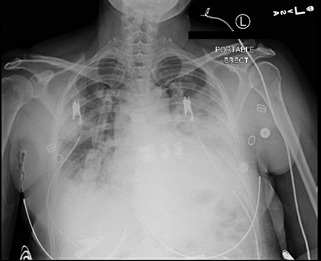

A 48-year-old woman with no past medical history presented with complaints of fever with sweats and chills, productive cough, and dyspnea with pleuritic chest pain for four days that progressively worsened to a point that she had difficulty completing sentences. She took over-the-counter nasal decongestants with no relief. On admission, vitals were significant for a temperature of 103.7 F, heart rate of 124 beats per minute, respiratory rate of 22 breaths per minute, and oxygen saturation of 92% on room air. Physical examination was significant for decreased breath sounds on the left base. A chest X-ray (Figure 1) showed left lower lobe pneumonia.

Laboratory investigations were significant for WBC of 13.5 x 103 /mm3 with 10% bands, blood and sputum cultures were drawn that remained negative, a polymerase chain reaction of nasal swab sample for methicillin-resistant staphylococcus aureus was negative. Influenza A (subtype H1) test was positive. Oseltamivir was started as well as azithromycin and ceftriaxone were started for a suspected superimposed bacterial infection. Due to persistent hypoxia, she was transferred to the intensive care unit (ICU) for oxygenation via a high-flow nasal cannula. A repeat chest X-ray (Figure 2) showed new opacities in the inferior right upper lobe and right base and small bilateral pleural effusions.